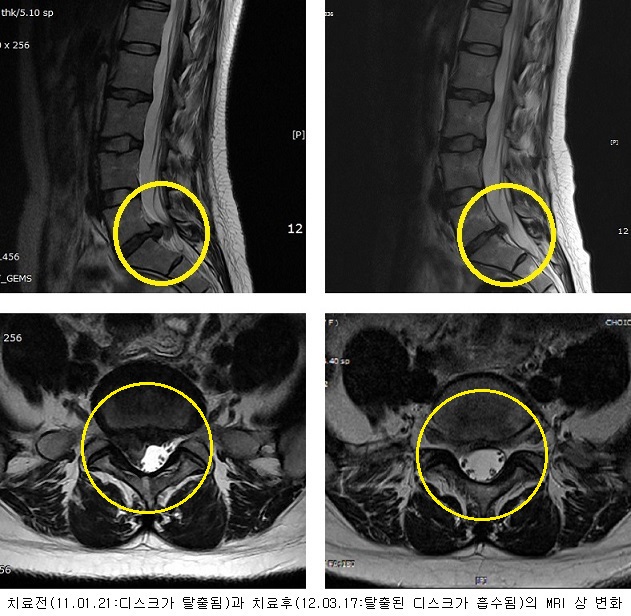

치료전후 MRI 비교

2012-03-17